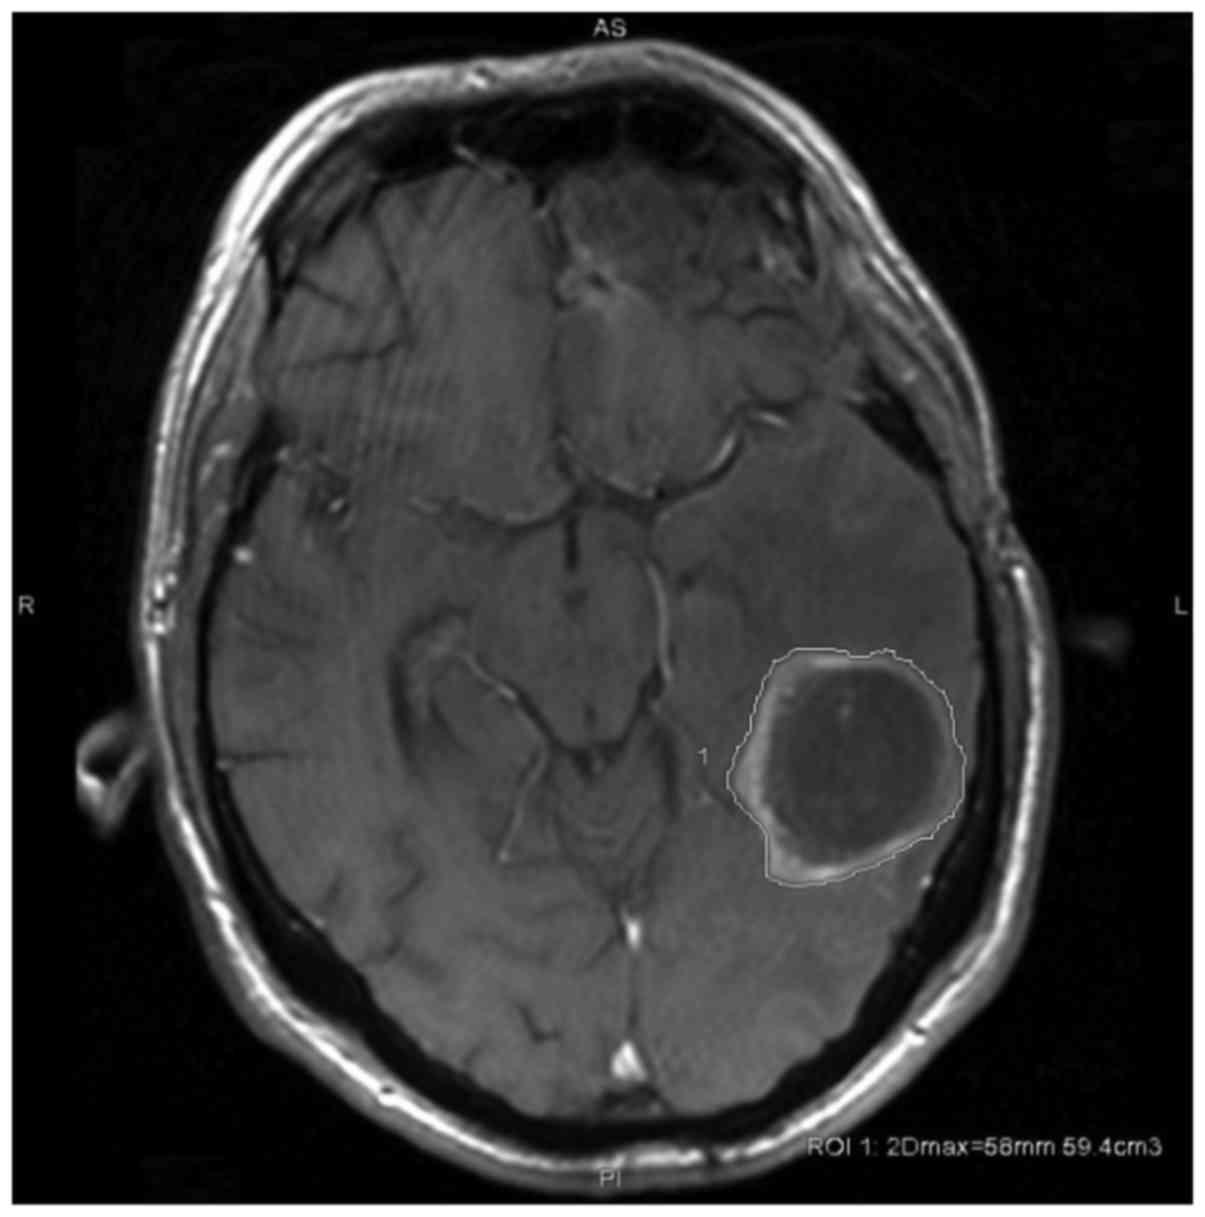

Magnetic resonance tumor volumetry. Volumetric analysis was performed on a GE Advantage Workstation (GE Healthcare Life Sciences, Little Chalfont, UK; version 4.7, Operation System 2.0 on a HELiOS 6.6.1 subsystem) by a radiologist. Tumor size and volume were calculated by semi-automated contouring of tumor borders on each T1 weighted-slice (post gadolinium) in cm3 and maximum 2D diameter in mm, as outlined in Fig. 2. Slice thickness was 1 and 5 mm, dependent on the subsequent protocols of MRI examination sequences applied between January 2012 and July 2017. Enhancing areas were considered as tumor with the exception of obvious vessels, artifacts or postoperative resection defects.

Figure 2.

Tumor size was calculated by semi-automated contouring of tumor borders on each T1 weighted-slice (post gadolinium) in cm3, and additionally maximum 2D diameter in mm.